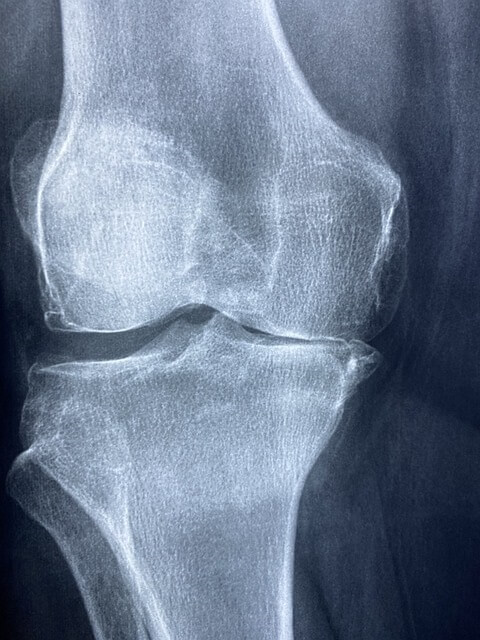

연골은 뼈와 뼈 사이에서 충격을 흡수하고 관절의 움직임을 부드럽게 하는 조직인데요.

콘드로이친은 이 연골의 수분을 유지하고 탄력을 제공하는 데 중요한 역할을 합니다.

콘드로이친은 관절염, 특히 골관절염의 증상을 완화하는 데 도움을 줄 수 있다고 알려져 있습니다.